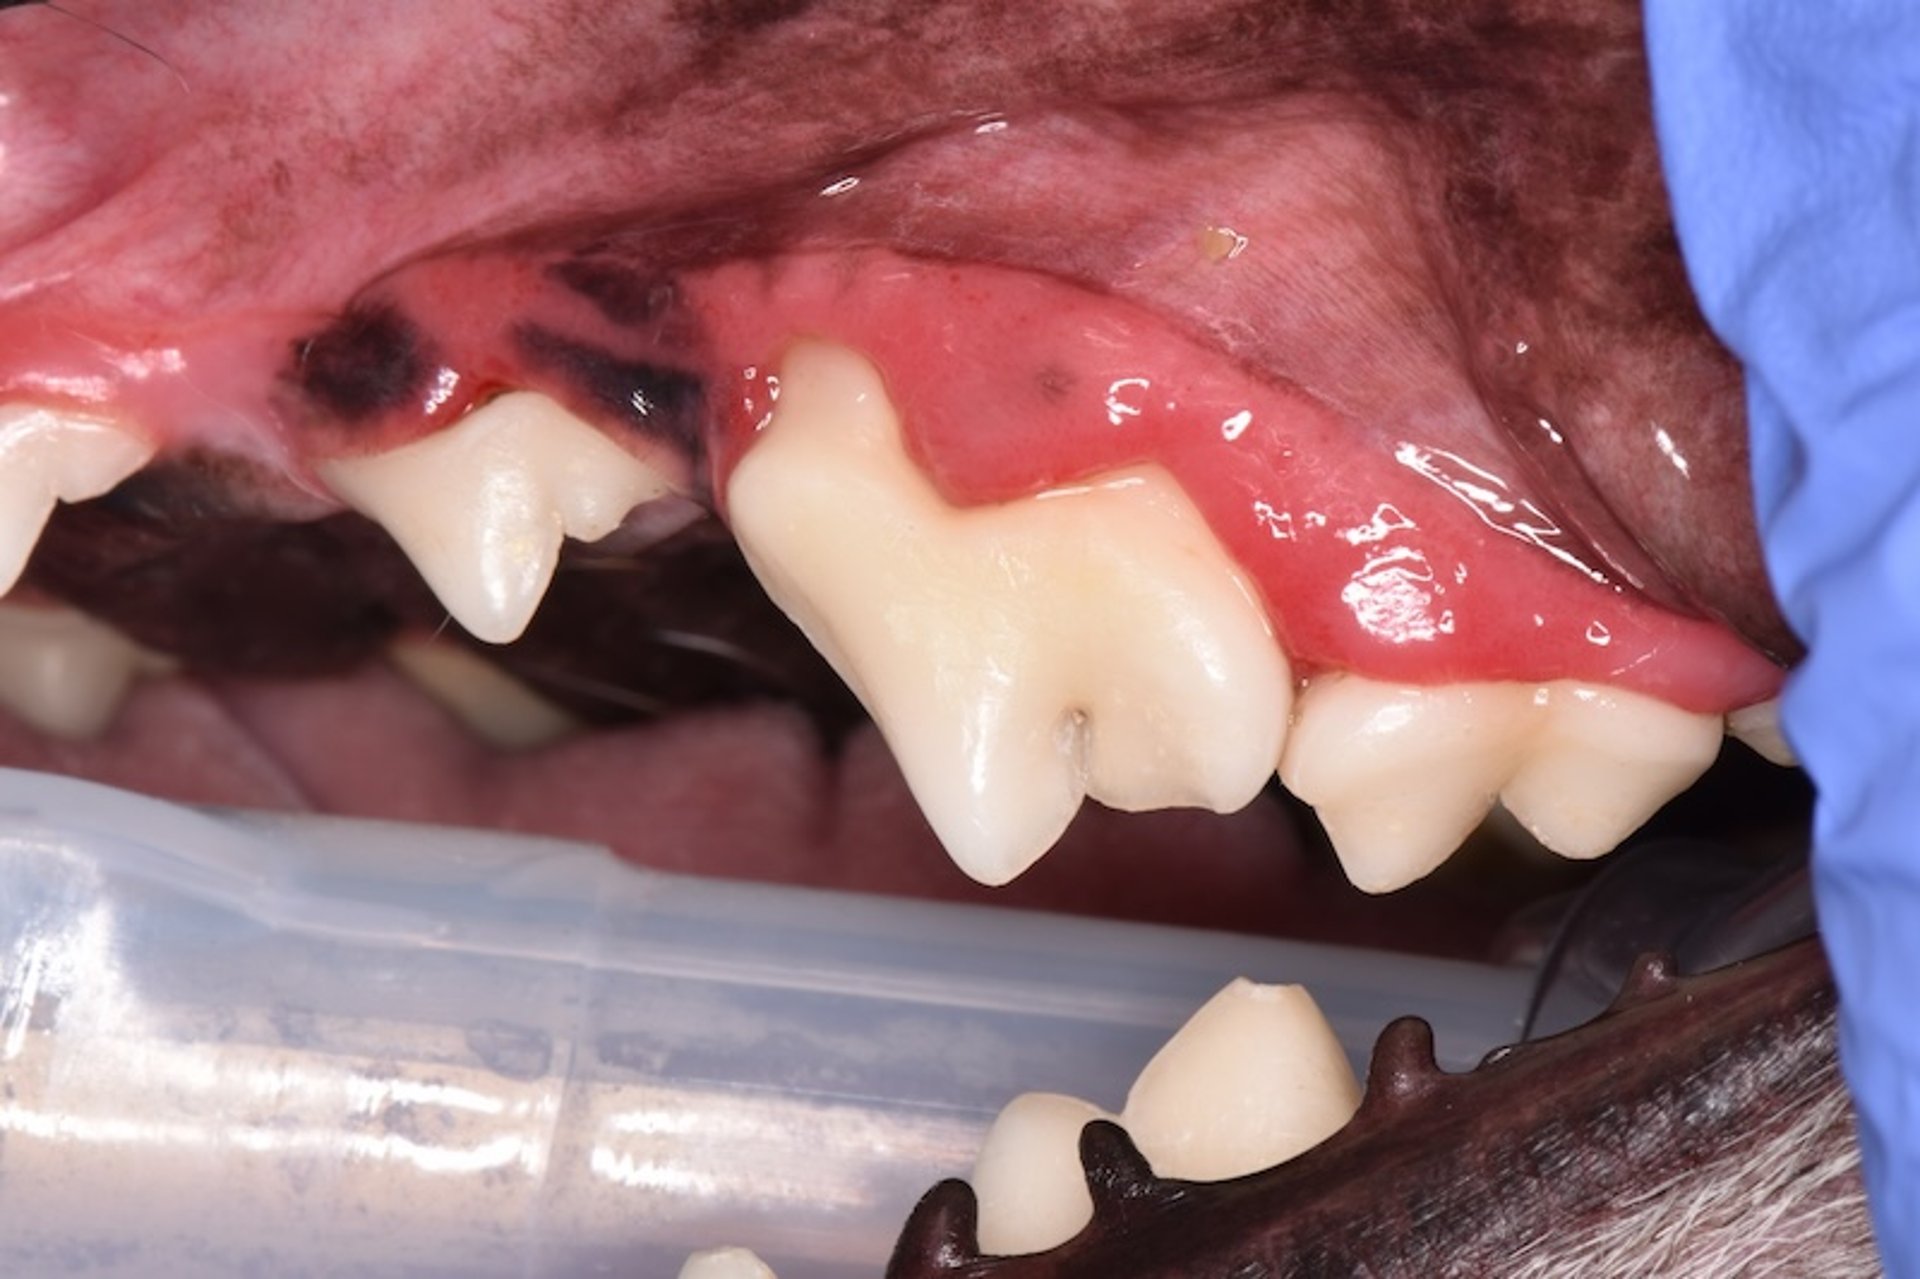

Periodontitis, gato

Gato con evidencia clínica de periodontitis y pérdida clínicamente aparante de encía, ligamento periodonyal y hueso alveolar. Obsérvese también la pérdida de inserción en este diente. El diagnóstico por imagen y el sondaje periodontal son necesarios para evaluar el estadio de la enfermedad periodontal.

Cortesía de la Dra. Brenda Mulherin.